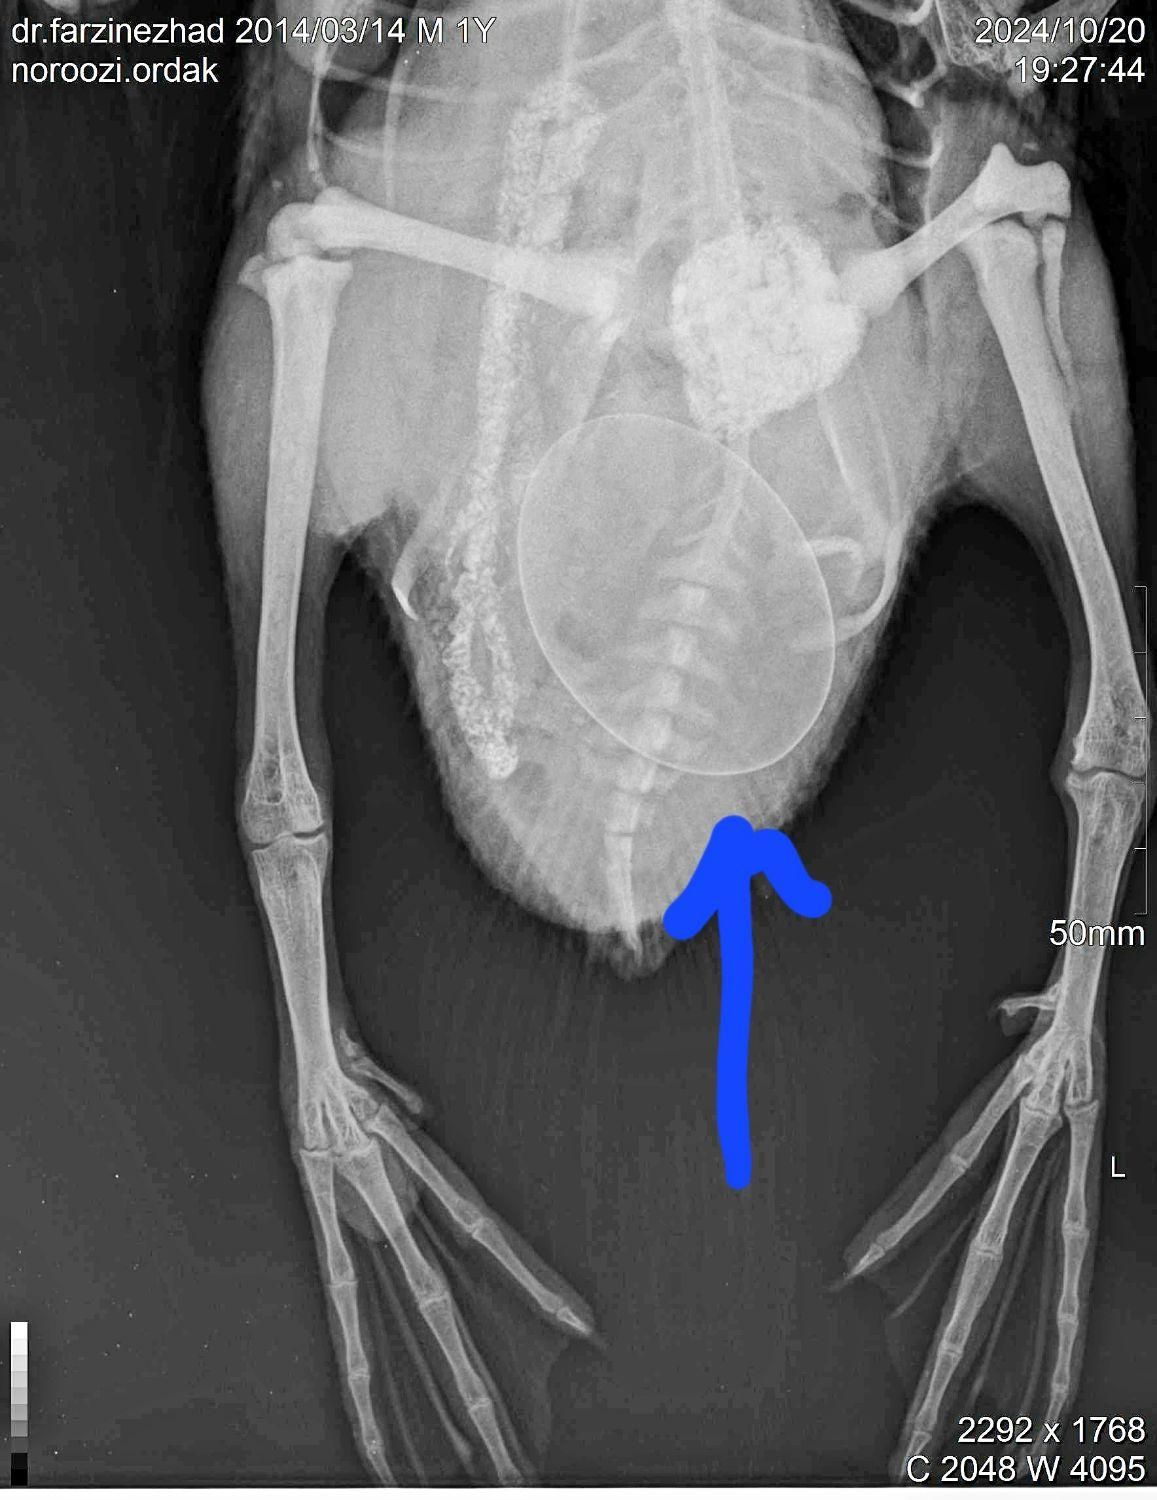

کلینیک دامپزشکی(سگ،گربه،رادیولوژی)دامپزشک

###لطفا و خواهشا قبل از مراجعه به کلینیک، جهت هماهنگی نوبت و ساعت تماس بگیرید### کلینیک دامپزشکی ( مرکز رادیولوژی و تصویر برداری تشخیصی دامپزشکی) دکتر زاهدزاده_اختصاصی حیوانات خانگی و پرندگان زینتی. دکتر حسین فرضی نژاد_رزیدنت بیماریهای داخلی حیوانات کوچک. 1.انجام هرگونه خدمات واکسیناسیون سگ و گربه. 2.انجام خدمات مخصوص پرندگان زینتی از قبیل تعیین جنسیت پرندگان، ویزیت، درمان، تزریقات، واکسن، اصلاح ناخن و بال، مشاوره جیره و نگهداری، جراحی های تثبیت شکستگی و غیره. 3.انجام خدمات درمانی سگ و گربه. 4.صدور شناسنامه و کاشت میکروچیپ(شناسنامه ثبت شده بین المللی). 5.صدور گواهی صحت سلامت و گواهی مسافرت هوایی داخلی و خارجی. 6.اخذ نمونه خون و ارسال به آزمایشگاه جهت تست های غربالگری و تشخیصی. 7.انواع جراحی ها از قبیل تثبیت شکستگی ها، عقیم سازی، پارگیها، چشم، جراحی های داخلی و ارتوپدی... 8.اصلاح و آرایش سگ و گربه. 9.رادیولوژی دامپزشکی(مرکز تصویربرداری تشخیصی). 10.انجام نبولایز پرندگان. آدرس کلینیک:خیابان سیمتری، خیابان جهرمی(کوچه جنب سینمابهمن)، نبش محمدیان،زیر مجتمع جلالی

تصویر 1 از 5